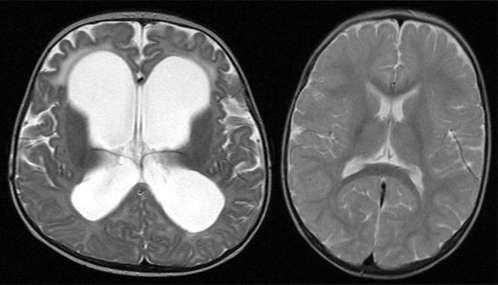

Для постановки точного диагноза недостаточно характерных неврологических симптомов – требуется обследование мозга. Чаще всего достаточно МРТ, на котором обнаруживается атрофия тканей мозга и увеличение объема ликвора. Однако в некоторых случаях необходимы дополнительные обследования.

Неврологи Юсуповской больницы для диагностики наружной заместительной гидроцефалии используют магнитно-резонансную и компьютерную томографию. Точное сканирование с возможностью получения трехмерного изображения сосудов, структурных изменений посттравматического характера, изучения коркового и мозгового вещества, гипофиза позволяет установить форму заболевания и степень повреждения мозговой ткани. Краниография (рентгенография черепа) позволяет определить деформации костей и канала зрительного нерва, наличие новообразований, обнаружить внутричерепную гипертензию.

Клиника неврологии Юсуповской больницы оснащена современным оборудованием, позволяющим быстро провести обследование пациента, получить точные результаты и выдать лечащему врачу заключение МРТ, картина наружной заместительной гидроцефалии на котором будет предельно ясна опытному специалисту.

Основным методом для установления диагноза наружная заместительная гидроцефалия головного мозга служит магниторезонансная томография черепа, которую, при обнаружении данного заболевания, в дальнейшем рекомендовано делать 2 раза в год.